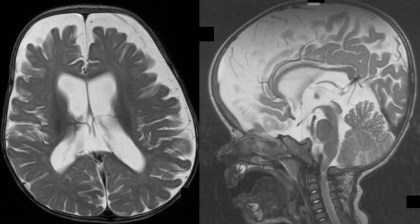

les problèmes hydrauliques de l’achondroplasie

ils sont classiquement dus à une compression veineuse au niveau des foramens jugulaires, rendue responsable de la macrocrânie habituelle chez ces patients.

Le PC est « normalement » augmenté dans l’achondroplasie. il existe donc des courbes de PC spécifiques des achondroplastes, garçons et filles.

cette expansion des espaces liquidiens peut favoriser la constitution d’une collection sous-durale post-traumatique.

les troubles hydrauliques peuvent intriqués avec un engagement tonsillaire, mais ils peuvent en être aussi bien la cause que la conséquence, ce qui laisse donc une place au traitement endoscopique.

il faut le plus possible éviter de mettre en place une valve, qui comporte un risque important de complications, du fait notamment de perturbations de la croissance crânienne.